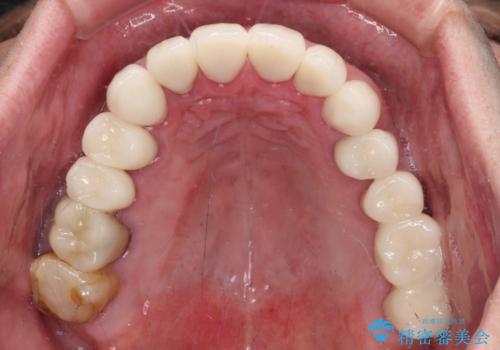

憧れの白い歯に 全顎セラミック治療

- 60歳を越え、黄ばんだ前歯をセラミッククラウンできれいな口元にしたいとのことで来院された患者様です。

診察したところ、前歯は反対咬合であり、その影響で抜歯が必要な奥歯があることが分かりました。

抜歯が必要な奥歯は、インプラント並びにブリッジにより補綴を行い、上下前歯は反対咬合を改善させるように補綴治療を行うこととしました。

健全な歯を削ってセラミッククラウンに置き換えることは、本来避けるべき治療と考えますが、今回は①患者様が60歳を越えていること、②要改善の咬合により抜歯が必要な奥歯があること、③反対咬合の前歯改善の手段としてセラミック治療が選択肢にあることなどから、全顎的なセラミック治療を行うこととしました。